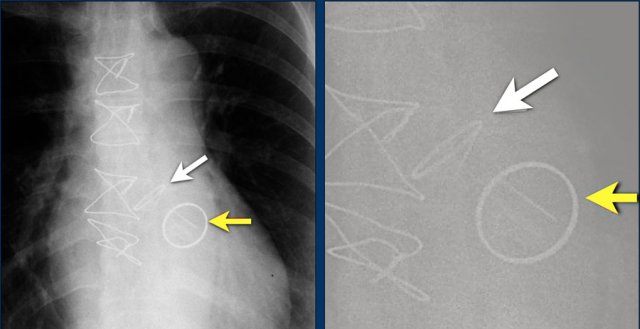

Here a patient with a normally placed ICD on the left image.

Months later there was malfunction due to ICD box and lead rotation (yellow arrow) and retraction (white arrow).

Here another patient with the Twiddler's syndrome.

Notice curling of the lead near the pacemaker and at the tip in the right ventricle (arrows).